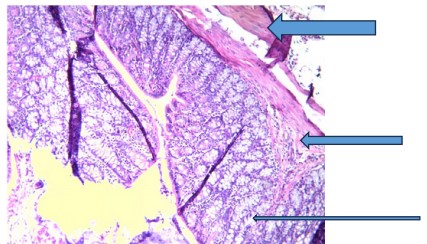

Sections of the colon tissues of rats exposed to 1,2-dimethylhydrazine revealed inflamed colon mucosa and tumor development in the colon when compared with control, which displayed normal mucosa (very thin arrow) consisting of columnar epithelium, lamina propria, and muscularis mucosa (Fig. 1). Also, the underlying submucosa (thin arrow) and muscularis propria (thick arrow) are essentially normal.

The irregularities detected in the DMH group, as shown in Fig. 2, are due to increased cell proliferation, apoptosis, and the formation of preneoplastic lesions and tumors18. Consequently, segments of colon tissues of rats administered V. amygdalina alone or before and after DMH induction revealed mild to moderate recovery from early signs of colon tumorigenesis, followed by reduced inflammatory cell infiltration as shown in Fig. 3-8, respectively. This suggests that the extract can improve colon histoarchitecture deformities because of its protective effects, which are characterized by bioactive components like flavonoids, saponins, and polyphenols present in it19.